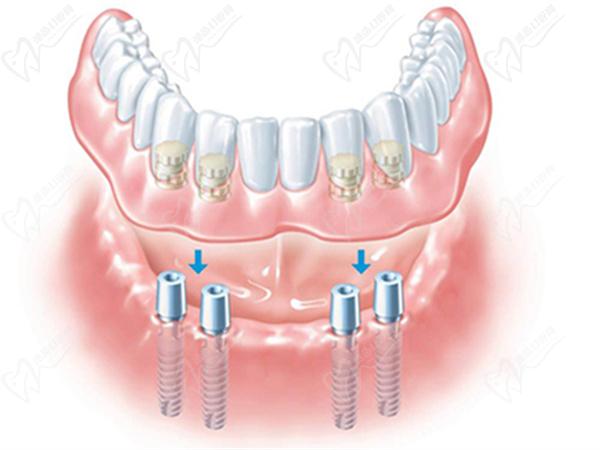

All-on-4是一种即刻种植牙技术,它指的是在全口牙齿缺失的情况下,通过在上下颌骨的4个位置植入种植体,以支持全口义齿或部分义齿的修复。

All-on-4种植牙

All-on-4主要适用于全口牙齿缺失的情况,还可以适用于牙槽骨密度较低或缺乏牙槽骨高度或宽度的患者。通过斜向的种植体布局,All-on-4技术可以充分利用可用的牙槽骨,并且不需要进行复杂的牙槽骨移植手术。这减少了手术的痛苦和恢复时间,使更多的患者能够享受到种植牙的益处。

All-on-4的植入方式相对复杂,需要在正规的口腔医院进行。首先需要对患者的口腔进行全方面的检查和评估,然后根据患者的具体情况制定个性化的手术方案。在手术中,需要通过切开牙龈组织和颌骨表面的骨膜,将种植体植入到骨组织中,然后再将牙龈组织缝合回去。整个过程中,患者需要接受全身麻醉,术后可能会有较明显的疼痛和肿胀,需要恢复一段时间。